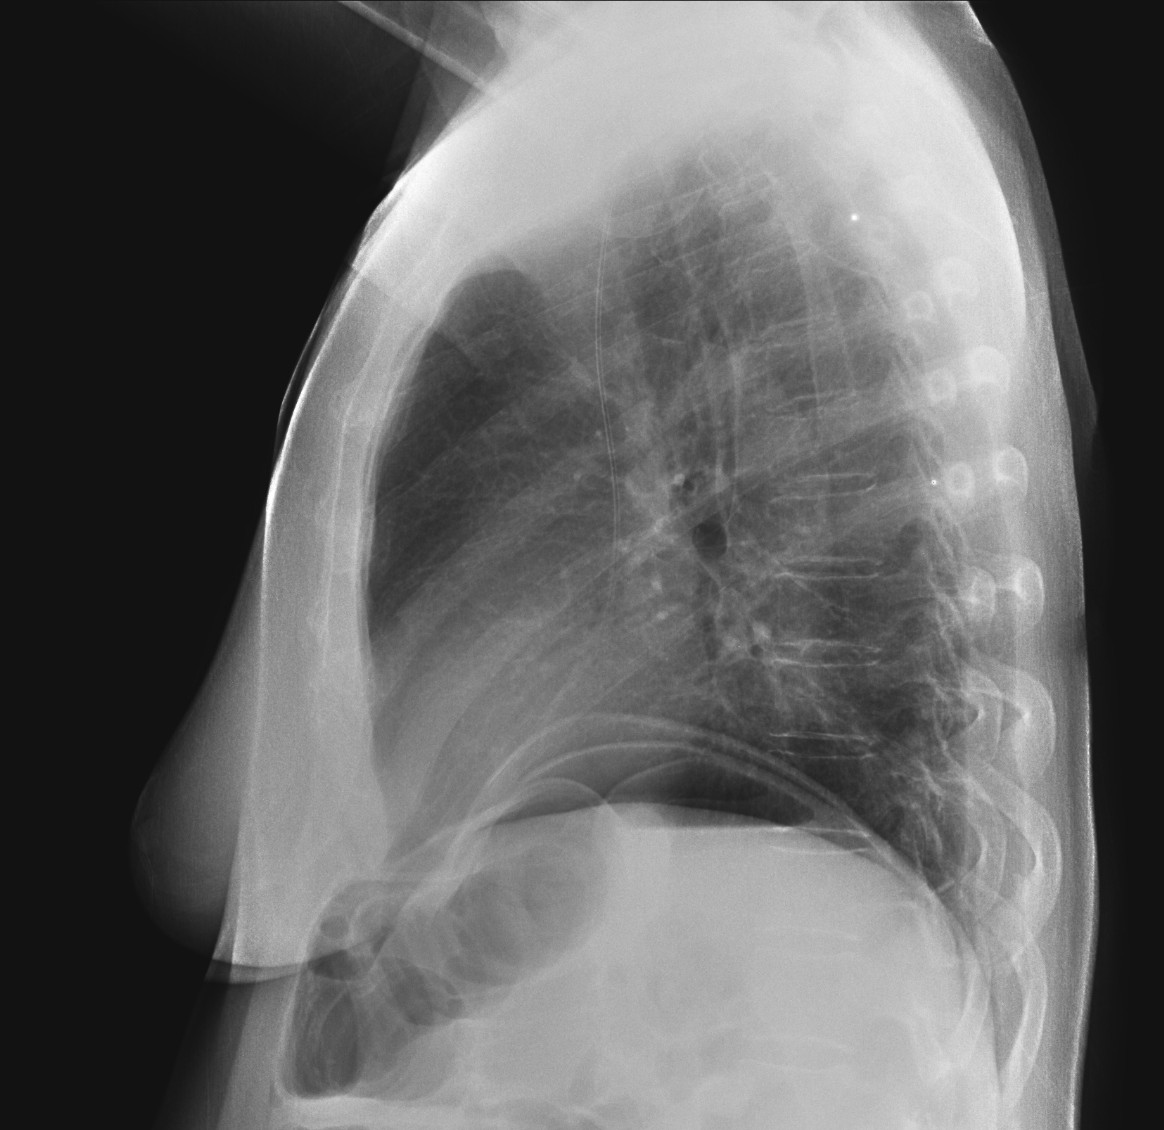

Paciente con diarrea y vómitos y dolor abdominal intenso. Antecedentes de fibrilación auricular. Analítica con discreta leucocitosis.

Se sospecha Isquemia intestinal. Veamos las pruebas complementarias de imagen:

En conclusión, estamos ante un cuadro de posible isquemia intestinal perforada, de ahí el neumoperitoneo.